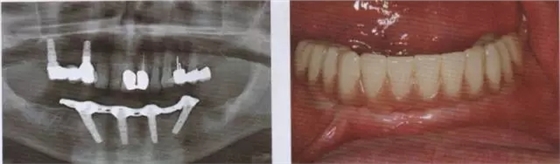

圖8 牙周病破壞了下合的牙齒系統(tǒng)

圖9 對牙周病破壞的下合員牙齒通過 CBCT數(shù)據(jù)進行帶角度的種植規(guī)劃.

圖10 在序列拔牙后及用生理益水中洗之前應(yīng)用光敏劑 (HELB0, bredent medlcal公司).

圖11 在手術(shù)快結(jié)束時放置印模t注用于制作即刻臨時修復(fù)體

圖12 戴入即刻l臨時修復(fù)體。

圖13 在取下上部結(jié)構(gòu)后可以看到完全無刺激反應(yīng)的軟組織

圖14 在下頜種植手術(shù)一年后可以看到種植體周圍骨水平穩(wěn)定且拔牙窩形成進一步的骨再生

圖15 在帶入終修復(fù)體后檢查,種植體完全無炎癥